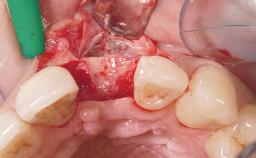

Late Flapless Placement of an Implant in a Maxillary Left Central Incisor Site

A 39-year-old male patient presented with a chief complaint of discomfort and gingival discoloration around his maxillary left central incisor. He was in good general health and was a non-smoker. His past dental history was significant because of the traumatic fracture of tooth 21 in a sporting accident at age 13. Initial dental treatment included endodontic therapy and a full-coverage restoration. The patient became symptomatic 5 years later, when structural failure of the tooth resulted in the dislodgment of the crown. Endodontic retreatment, apical surgery, and post-and-core restoration were performed.

Bone Augmentation Horizontal|Staged

Bone Volume Deficient horizontally, requiring prior grafting